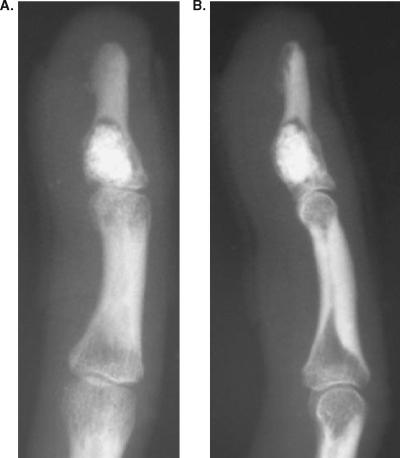

This case report describes an enchondroma of the distal phalanx of the right little finger in a 37-year-old woman with Camurati-Engelmann disease. Curettage of the tumor and artificial bone grafting were performed in May 2004. Surgical treatment resulted in a good clinical outcome with no evidence of recurrence at 5-year follow-up. The genetic relationships between Camurati-Engelmann disease and benign chondroid tumors are discussed.

本病例报告描述了一名 37 岁女性的右手小指末节内生软骨瘤,该女性患有 Camurati-Engelmann 病。2004 年 5 月,对肿瘤进行了刮除和人工骨移植。手术治疗后,患者临床疗效良好,5 年随访未见复发。讨论了 Camurati-Engelmann 病与良性软骨样肿瘤之间的遗传关系。